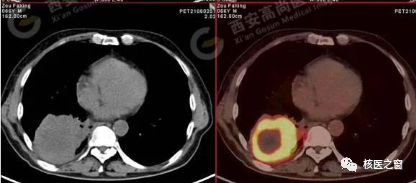

PET/CT的檢查原理是將放射性藥物注入體內(nèi),再通過PET/CT對身體內(nèi)不同器官中放射性藥物所發(fā)出的射線進(jìn)行采集、成像,然后再根據(jù)所成圖像的特點(diǎn)來進(jìn)行診斷。而在檢查時(shí),如果患者攜帶金屬物質(zhì)躺在檢查床上,那么放射線的行進(jìn)則會受到金屬的阻礙,從而導(dǎo)致機(jī)器探測到的放射性不準(zhǔn)確,進(jìn)而使圖像失真,影響檢查效果。另外,小編在這里還要提醒一下,朋友們?nèi)绻龅臋z查是PET/MR,那么金屬物品是一點(diǎn)都不可以帶入機(jī)房的!